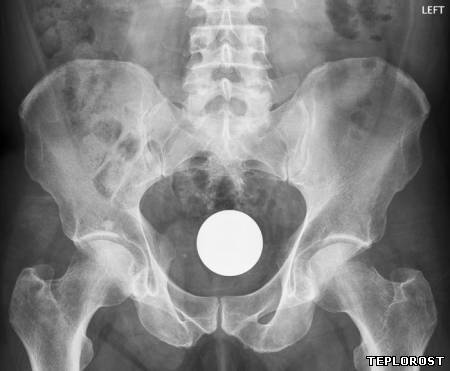

Редкие снимки от врачей-рентгенологов. Фото реальных снимков на рентгеновском аппарате.

Застрявший в прямой кишке вибратор.

Бильярдный шар во влагалище.